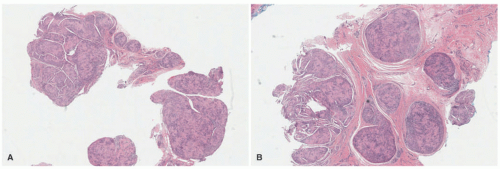

FIGURE 24-26. A-C, Dermatofibrosarcoma protuberans. Fibrohistiocytic proliferation with near total replacement of the dermis and infiltration of the subcutaneous fat (A). Uniform, compactly arranged, spindle cells in fascicles and/or storiform profiles that replace the dermis and extend in a confluent fashion into the subcutis (B and C). Digital slides courtesy of Path Presenter.com.

One of the consistent histologic features if the biopsy includes the subcutis is the near total replacement of the dermis and infiltration of the subcutaneous fat (Figure 24-26). The latter finding is not specific to DFSP because it is also present in diffuse NF and some of the fibrous tumors in an infant or young child. The classic pattern of DFSP consists of uniform, compactly arranged, spindle cells in fascicles and/or storiform profile, which replace the dermis and extend in a confluent fashion into the subcutis (Figure 24-27A-C). Fusiform cells have uniform nuclei with minimal pleomorphism and sparing mitotic activity. In addition to this basic pattern, myxoid and/or collagen-rich foci may be seen as adjoining foci with the classic pattern or as the exclusive pattern in some cases. The presence of scattered multinucleated giant cells in clefted or pseudovascular spaces in a spindle cell background or loose fibrous stroma are the features of GCF (Figure 24-28A-C). The GCF pattern can be localized in a DFSP with classic or fibrous features, may represent the exclusive pattern, or is present as the initial histologic feature in a tumor that recurs with classic, myxoid, or fibrous features.113 Pigmentation of tumor cells is uncommonly present in DFSP in the so-called Bednar tumor. Immunohistochemistry is a useful adjunct to the diagnosis of DFSP as long as it is understood that other dermal and subcutaneous spindle cell tumors are CD34+.122 Typically, CD34 staining is uniformly and diffusely positive (Figures 24-29 and 24-30), but other markers have been reported to facilitate the diagnosis including CD99, D2-40, and apolipoprotein

FIGURE 24-27. A-D, Dermatofibrosarcoma protuberans on the trunk of a 4-year-old male. A, Infiltration of tumor into the subcutis shows the overgrowth pattern. B, Another focus of this tumor shows a similar overgrown pattern, but note its more fibrous, hypocellular appearance. C, This focus shows scattered, enlarged tumor cells. D, The so-called honeycomb pattern of tumor growth is present in this focus.

FIGURE 24-28. A-C, Giant cell fibroblastoma (GCF) presenting in the breast of a 7-year-old female. A, Numerous multinucleated giant cells with pericellular clear space are accompanied by a neoplastic fibrous stroma. B, Another area in the same neoplasm shows a diffuse fibrous pattern of this tumor. Most GCFs arise in a similar fibrous pattern. C, This GCF from the trunk of a 4-year-old male shows the exaggerated pseudoangiectoid pattern.